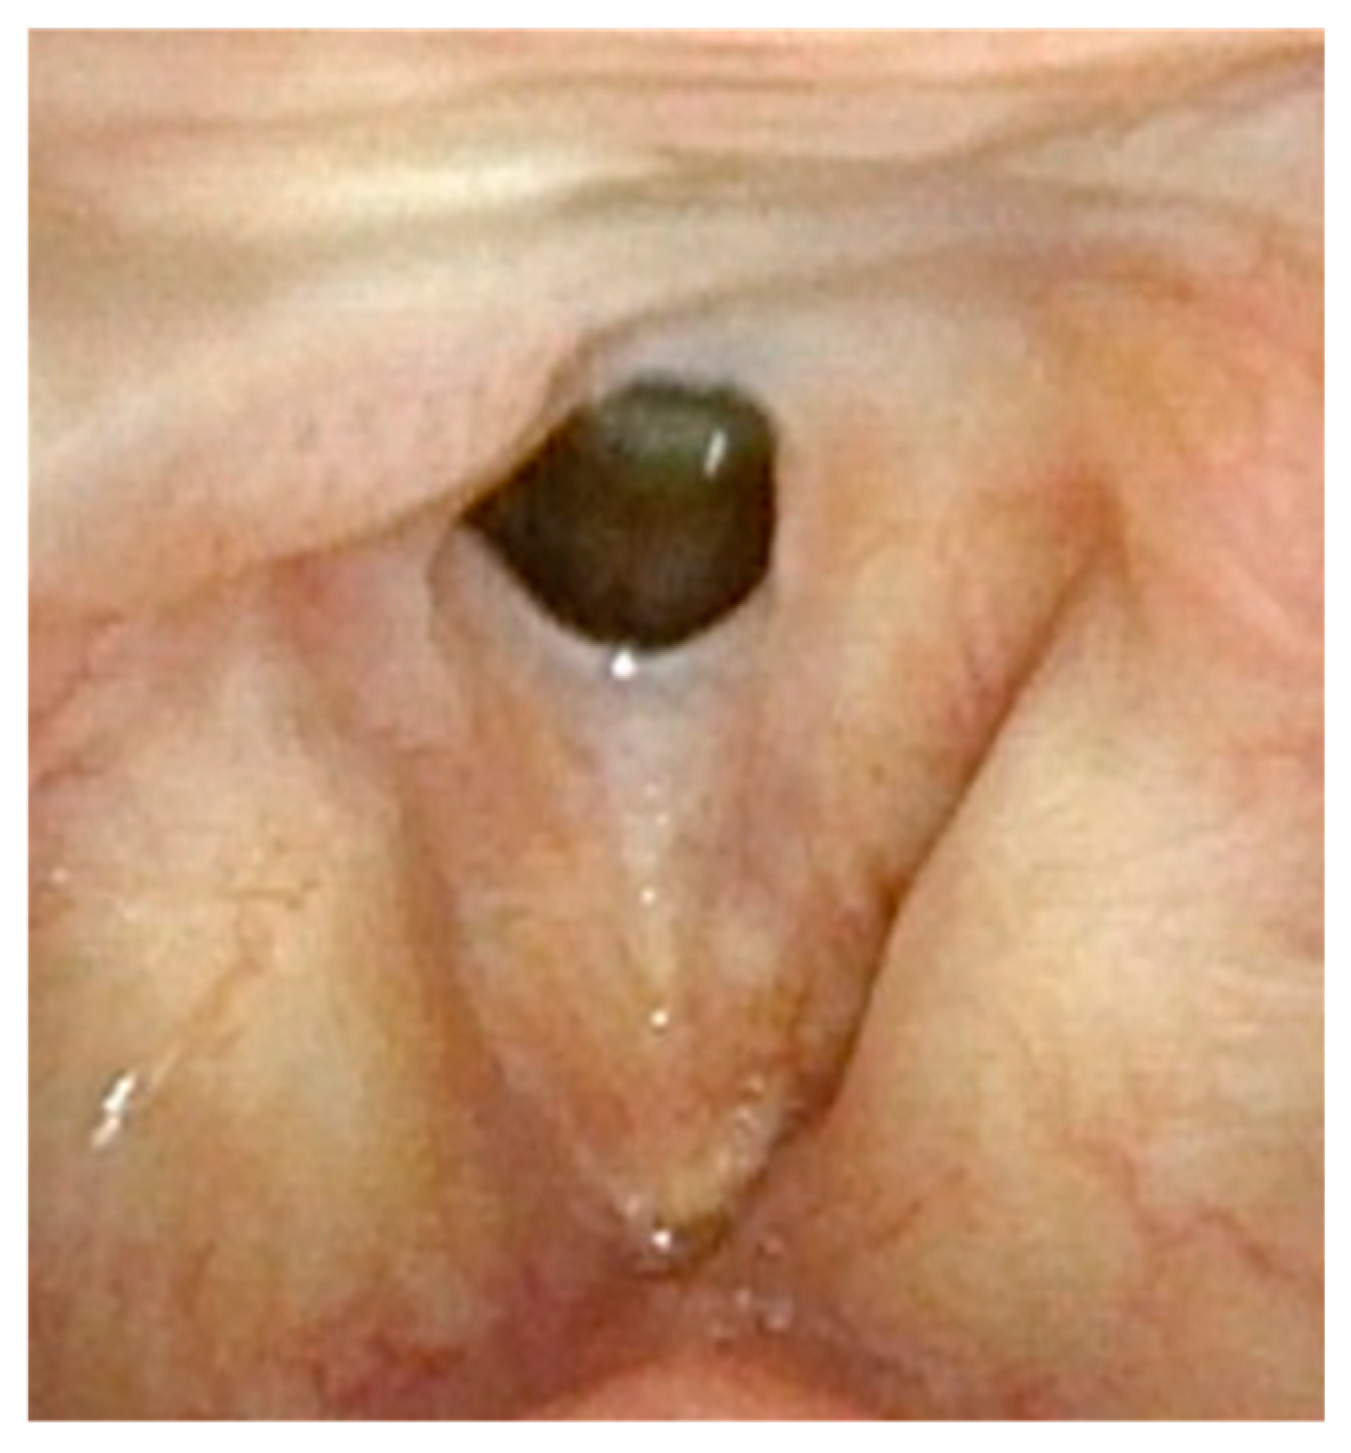

Figure 1 demonstrates a patient who had too aggressive anterior commissure laser treatment. A consequence of this was a very large anterior glottic web. Should this be encountered, the web may be lysed in the midline and steroid-injected (Figure 2). If the web is not the full thickness of the vocal folds, it should be cut with cold steel to help prevent the return of the web during healing. Once healed the web should be significantly improved (Figure 3). Consideration should be given to the dilation of the glottis following lysis.

Figure 1.

Large anterior glottic web with small amount of papilloma on right posterior commissure.

Figure 2.

One week post-op following laser ablation of laryngeal papilloma and lysis of anterior glottic web.

Figure 3.

Three months post-op following laser ablation of laryngeal papilloma and lysis of anterior glottic web. The majority of the anterior glottic web is resolved, but there is already regrowth of papillomas.